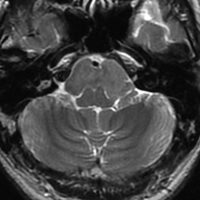

典型的な神経腸嚢胞 neurenteric cyst

左のT2強調画像で等信号,中のT2*で高信号,右はCISS画像です。

T1強調画像では,のう胞周囲の高信号の部分は半固体で,中心部の高信号はドロドロの粘液でした。基本的にガドリニウム増強はされません。まれに薄い膜状に一部が増強されることがあります。

境界明瞭は袋状の腫瘍です。椎骨動脈や脳底動脈を包み込むようにふくらんでいます。